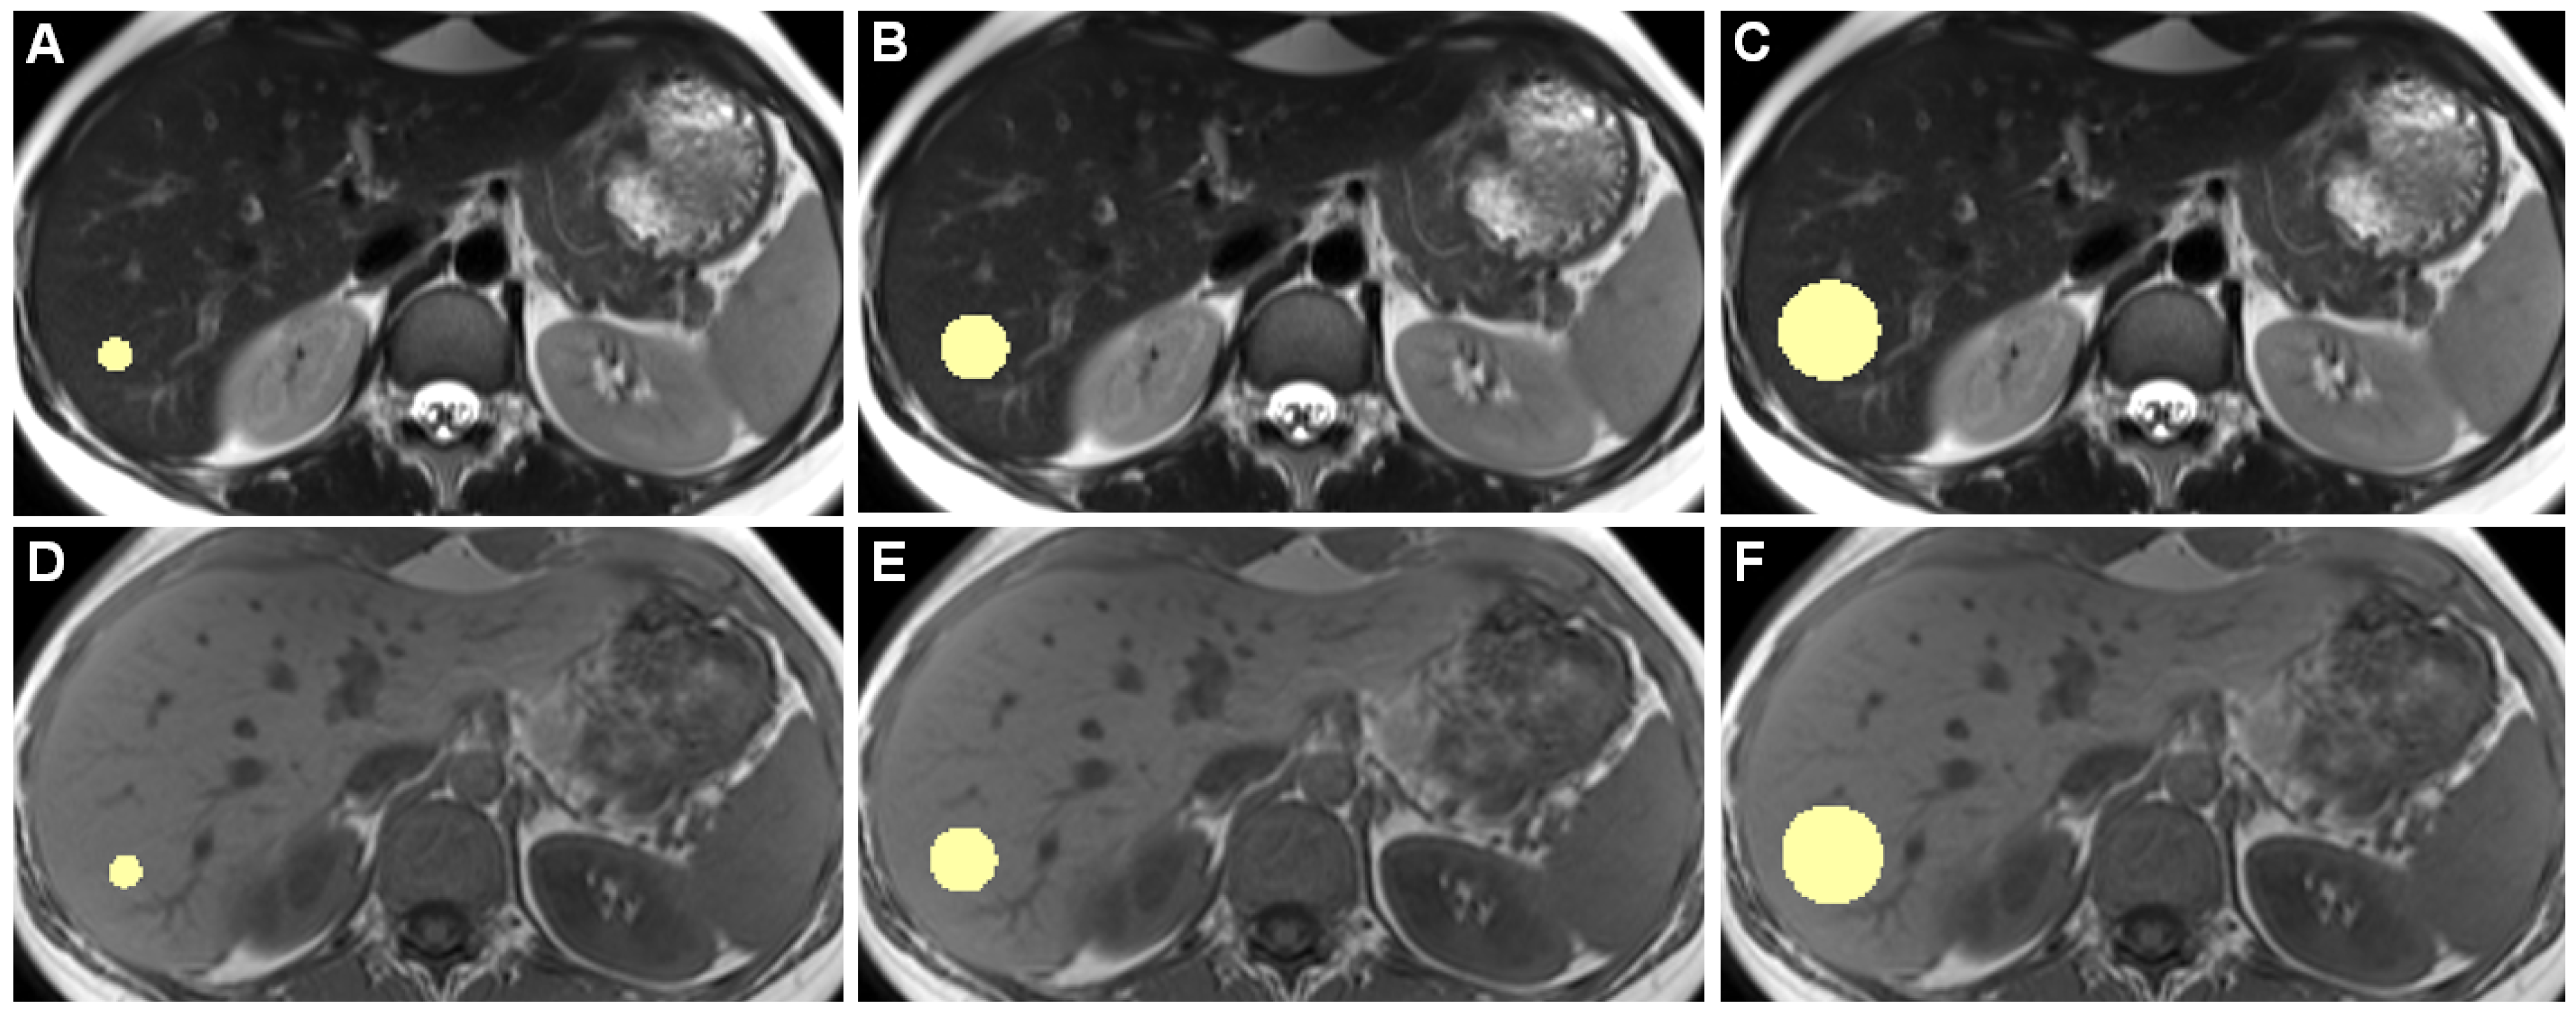

Figure 1 shows example slices of a 3D ROI.

Figure 1.

Example slices of 3D ROIs of one healthy individual, acquired on the 3 Tesla I scanner, are shown. Images (A–C) are from a T2-weighted TSE HASTE sequence, (D–F) are from a T1-weighted GRE FLASH sequence. (A,D) show 10-mm diameter ROIs, (B,E) 20 mm, and (C,F) 30 mm ROIs. While drawing ROIs manually throughout all included patients, we aimed to only include hepatic parenchyma while excluding any apparent blood vessels or bile ducts.